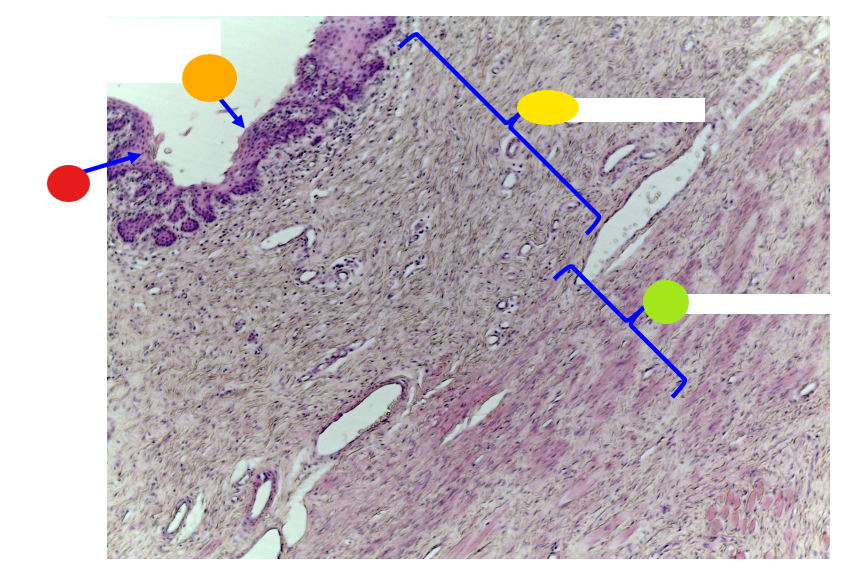

red

serosa

orange

lumen

yellow

mucosa

light green, name and tissue type

muscularis, smooth muscle

dark green

serosa

What is this?

uterine tube

red

lamina prioria

orange

simple columnar epithelium

yellow

lumen

what is this?

uterine tube

What tissue type is the epithelium/inner linning of the uterine tube?

simple columnar epithelium